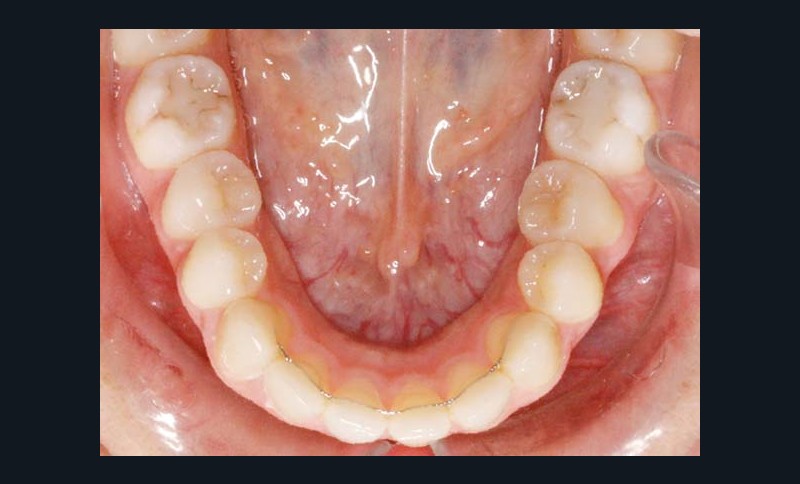

La patiente est appareillée en technique autoligaturante passive vestibulaire, Damon Clear (Ormco) au maxillaire et Damon Q (Ormco) à la mandibule avec sélection individualisée des torques selon les angulations radiculaires et des arcs .014 NiTi thermiques sont mis en place.